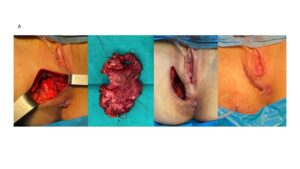

Surgical removal of the mass was performed, aiming for macroscopically clear margins while prioritizing preservation of adjacent organs. No intra- or postoperative complications occurred. Pathology confirmed the diagnosis and reported involved margins, indicating microscopic residual tumor.